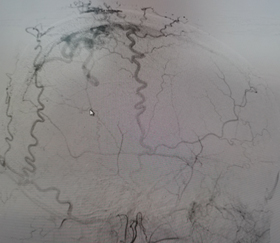

腦血管病診療中心聚集了一批擁有豐富臨床經(jīng)驗(yàn)和深厚學(xué)術(shù)背景的腦血管病專家。中心專注于腦血管疾病的預(yù)防、診斷、治療及康復(fù),主要診治各類腦血管疾病,如顱內(nèi)動(dòng)脈瘤、蛛網(wǎng)膜下腔出血、腦血管畸形、煙霧病、硬腦膜動(dòng)靜脈瘺、顱內(nèi)靜脈系統(tǒng)疾?。ㄈ珈o脈竇血栓、靜脈梗塞引起的腦梗死或腦出血)、外傷或自發(fā)性海綿竇內(nèi)動(dòng)靜脈瘺(CCF)、脊髓內(nèi)血管畸形、髓周動(dòng)靜脈瘺、硬脊膜動(dòng)靜脈瘺、腦和脊髓的海綿狀血管瘤,顱內(nèi)血管狹窄、頸動(dòng)脈狹窄、椎-基底動(dòng)脈狹窄、鎖骨下動(dòng)脈狹窄、顱內(nèi)和頸部的血管夾層、顱內(nèi)或頸部血供豐富的腫瘤術(shù)前栓塞或化療等。從疾病的早期篩查、診斷到治療及后期康復(fù),我們提供全面的診療服務(wù)。